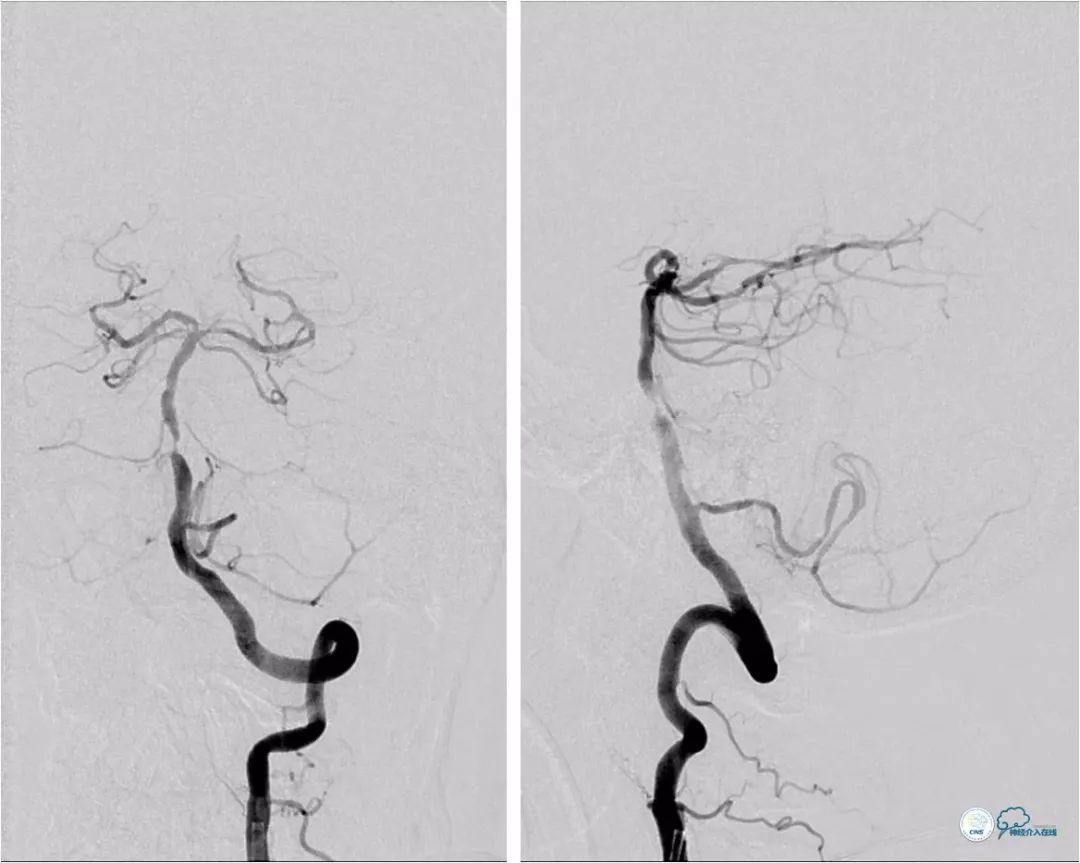

DSA:左椎动脉优势,左椎动脉V1段重度狭窄,右椎动脉V1段中度狭窄,双椎动脉V4-基底动脉下段重度狭窄,狭窄率约为85%,狭窄段有AICA发出,双侧后交通动脉未开放(图6-9)。

后置入Wingspan自膨式支架(3.5×15mm),造影提示支架释放后支架贴壁良好,前向血流TICI 3级(图14)。

图14

本例技术难点在于先放置左椎开口支架后,如何将导引导管越过支架,放置左椎动脉V2段远端。我们操作与既往报道的病例类似,放置支架后,低压充盈球囊,缓慢前送导引导管,如果椎动脉开口定位准确,且近端没有明显血管迂曲,类似的操作一般都能成功。放置近端支架前,我们先小球囊扩张狭窄,目的是降低随后置入球囊支架时的支架移位几率。当然本例也可以先行近端球囊扩张,跟进导引导管,待处理完基底动脉病变后,再放置近端支架。